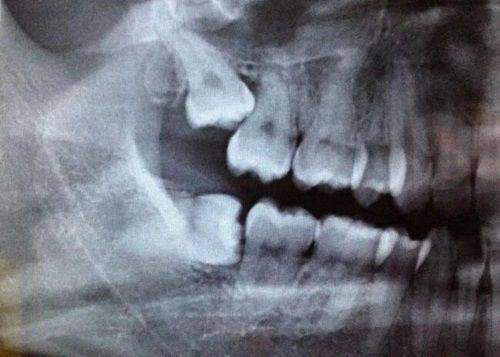

在设备上,医院注重引进高端的医疗设备和技术,配备了数字化口腔成像系统、口腔CT扫描仪、激光治疗设备等多种可靠的口腔诊疗设备,能够支持复杂的种植牙手术和其他口腔治疗项目。

平凉三旺口腔医院的诊疗项目丰富多样,涵盖镶牙种植牙、牙齿矫正、牙齿美白、牙周病治疗、补牙、儿童牙科、口腔颌面外科、口腔修复、口腔正畸、口腔种植、预防口腔等。还设有医学检验科(临床体液、临床化学检验)、医学影像科(X线诊断、CT诊断、心电诊断)等。